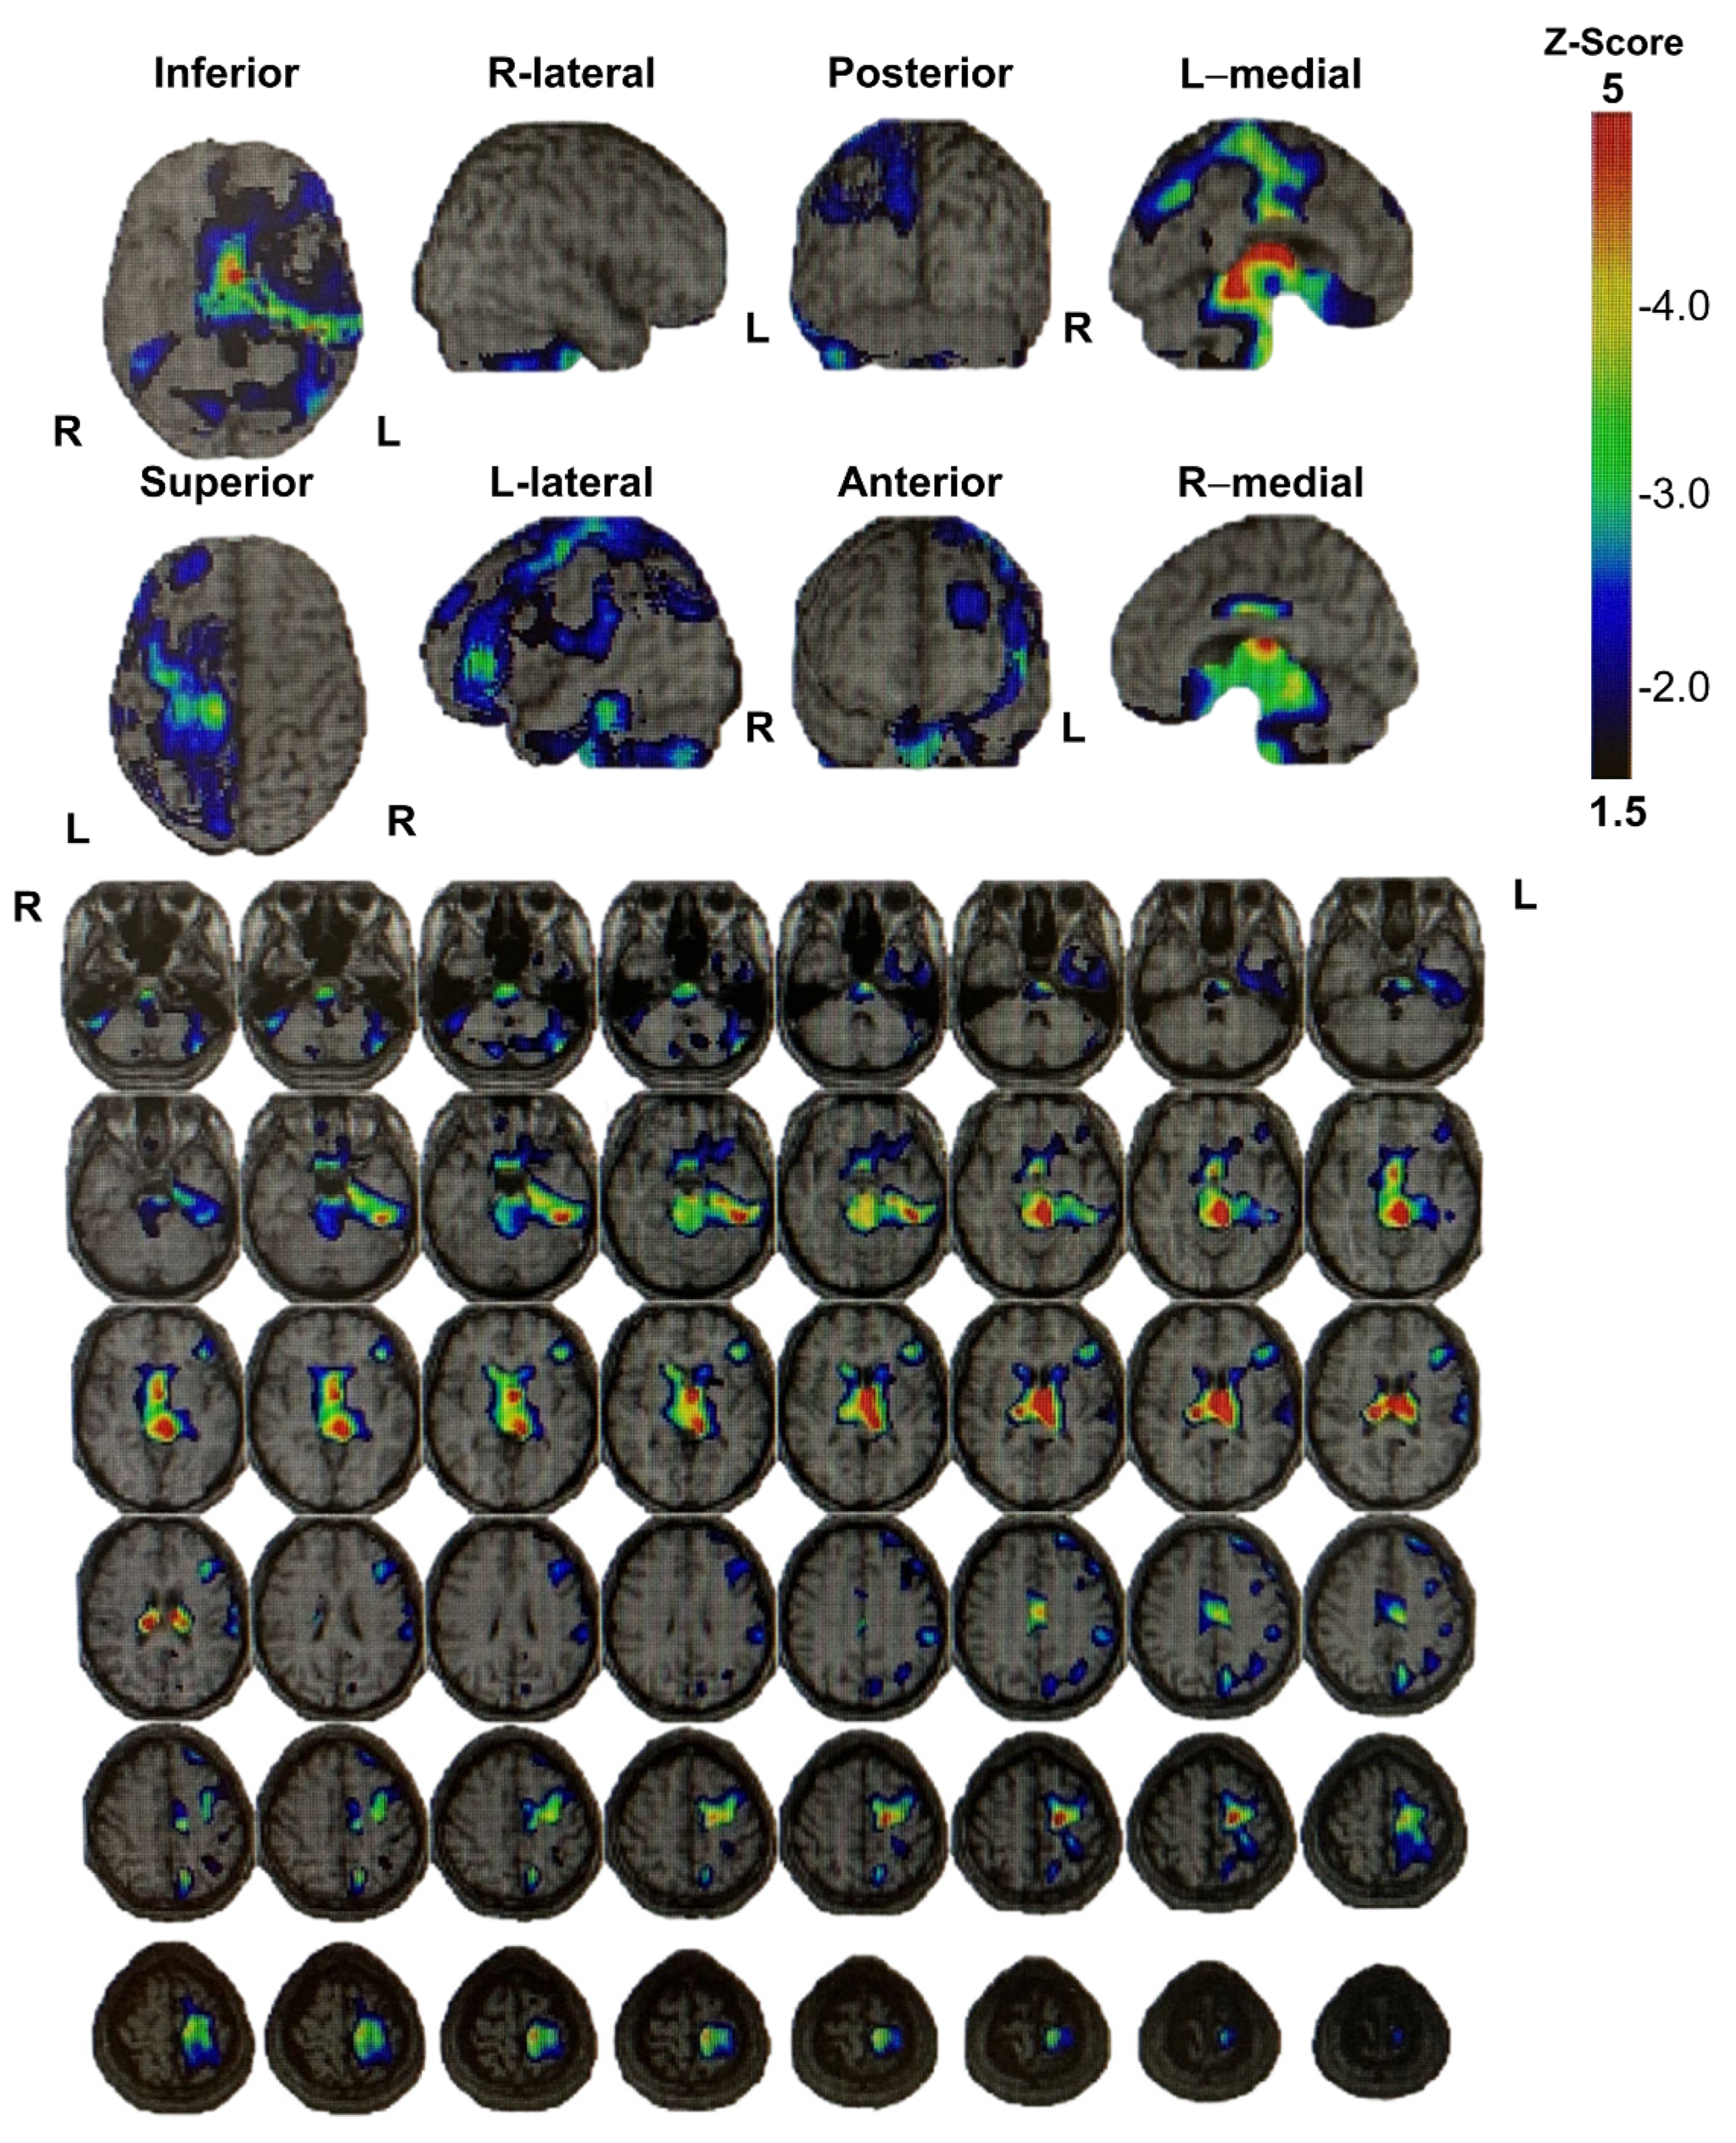

4. Discussion and Conclusions

Mechanism Underlying the Pathogenesis